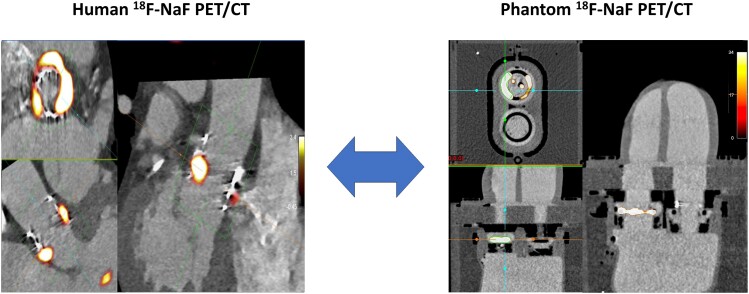

Methods and results: We placed a bioprosthetic valve with two pockets sutured to the leaflets mimicking valvular lesions and a subvalvular ring mimicking the valve remnant into the phantom and injected each with 18F-radionuclide (1 μCi pockets, 4 μCi ring). We injected the cardiac chambers with iohexol and 18F-radionuclide (0.176 mCi) for background activity. PET and computed tomography (CT) images were acquired using a Siemens Biograph Vision high-resolution digital PET/CT scanner. We analysed target-to-background ratio (TBR) and signal-to-noise ratio (SNR) and subjective measures of image quality. We compared results with a human case of transcatheter aortic valve replacement. Initially the SNR and TBR in the phantom greatly exceeded those from human imaging. We reduced the scan duration used for reconstruction to 30 and 15 s, achieving comparable results (30 s vs. 15 s vs. patient: SNR 45.6 vs. 13.9 vs. 44.3, TBRmax 6.5 vs. 5.4 vs. 4.1, noise 10.2% vs. 8.8% vs. 12.0%). With motion correction, SNR and image quality improved in the phantom (30 s 135.8 vs. 45.6, 15 s 32.9 vs. 13.9) but remained similar in the human case (47.3 vs. 44.3).

Conclusion: A cardiac phantom can mimic clinical 18F-NaF valve bioprosthesis imaging, providing an opportunity to explore acquisition, reconstruction, and post-processing of 18F-NaF PET/CT for small mobile cardiac structures.